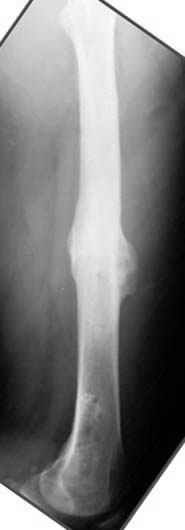

Если, например, доводится лечить больных с псевдартрозами шейки бедра, то надобность есть, и приходится. См. приложение.

Несколько снимков из моей коллекции, чтобы разьяснить, почему мы до сих пор делаем различные варианты остеотомии.

На рисунке N1 предоперационный план лечения ложного сустава шейки бедра- линия ложного сустава, угол и направление введения импланта, клиновидная остеотомия в градусах и миллиметрах, второй снимок после коррекции, расчет, на сколько удлиняется конечность и размеры импланта;

N3 рисунок окончательный снимок, после операции моя рентгенограмма должен выглядеть примерно как эта картина. На N4 снимке клин перед удалением; N5 послеоперации 3 нед.; N6 окончательная рентгенограмма.

Отправитель: Djoldas Kuldjanov 23 Ноябрь 2004, 18:21

пластическая модель; и коррекция бедра аппаратом Илизарова.

Узкий к-м канал - тонкий гвоздь- усталостный перелом дистальных винтов - развитие нестабильности и как ее результат остеолиз вокруг гвоздя - деформация анатомической оси бедра. Похоже, что я понял почему аппарат, а не новый гвоздь:-)